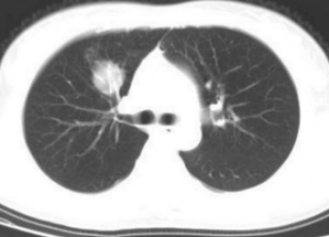

但,此后咳嗽、咳痰症状持续存在,虽服用多种抗感染药物,缓解效果均不佳。患者遂至该院呼吸科门诊就诊,经胸部CT检查提示左下肺阻塞性肺炎,随即入住呼吸与危重症医学科。

入院后,科室根据患者胸部CT表现,初步评估病灶位于左肺下叶内基底段某个亚支。该部位依靠常规的支气管镜检查难以触及,为进一步确定病灶位置,结合患者薄层CT,手绘病灶所在支气管各亚段及亚段导航图,利用径向超声小探头进行检查,终于发现了准确的病灶位置。